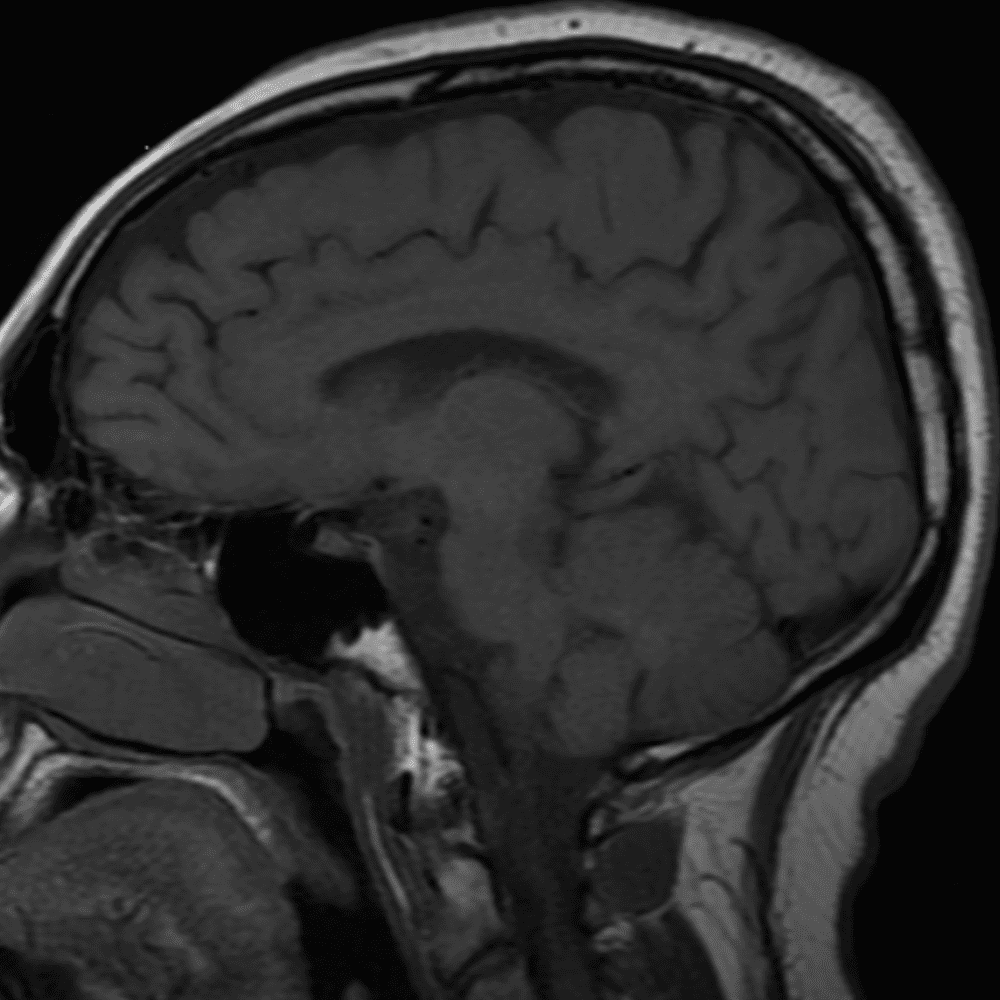

๋‹น์ง ์‹œ ํ”ํžˆ ๋ณผ ์ˆ˜ ์žˆ๋Š” ์‚ฌ๋ก€์˜ ์ „ํ˜•์ ์ธ ์˜ˆ๋ฅผ ํฌํ•จํ•ฉ๋‹ˆ๋‹ค.

39 ์‚ฌ๋ก€

์—ฐ์Šต

๋ฏธ๋ฌ˜ํ•˜๊ฑฐ๋‚˜ ์–ด๋ ค์šด ์‚ฌ๋ก€์™€ ์ผ๋ถ€ ์ •์ƒ ์‚ฌ๋ก€๋ฅผ ํฌํ•จํ•˜์—ฌ ๋‹น์ง์„ ์‹œ๋ฎฌ๋ ˆ์ด์…˜ํ•ฉ๋‹ˆ๋‹ค.

50 ์‚ฌ๋ก€